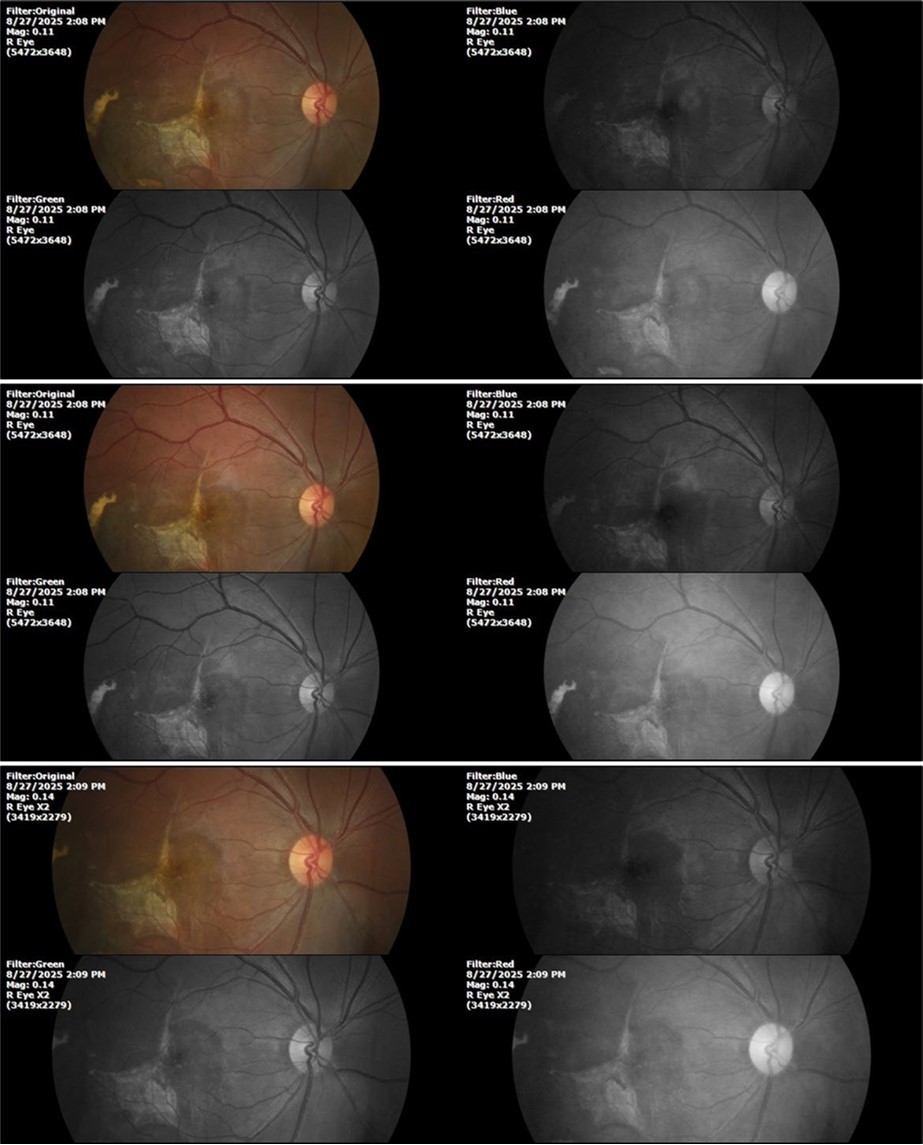

August 26, 2025

It's been fine, there's only a little veil that prevents it from seeing well completely, although it's very transparent (Figure 31, Figure 32, Figure 33, Figure 34, Figure 35, Figure 36).

Figure 31.The photograph of the right eye shows an almost normal mirror reflection, as well as a better pupillary dilation.

Figure 32.The macro photograph of the right eye shows us a cornea, anterior camera, and crystalline lens in very good condition.

Figure 33.The 3 previous photographs show that whitish mass has almost completely disappeared, and to date only a remnant remains on the left side of the photograph. The chorioretinal scar that is now observed corresponds to the area affected by the blunt trauma, which presumably caused rupture of Bruch's membrane. Fortunately, the macular region has recovered almost in its entirety, so the impairment in central vision was minimal.

Figure 34.The mirror reflection of the healthy eye (L. E.) continues within normal limits.

Figure 35.The anatomy of the anterior segment of the left eye is shown without alterations.

Figure 36.The retina, optic nerve, choroid, and macula of the left eye do not show any evidence of sympathetic ophthalmia.